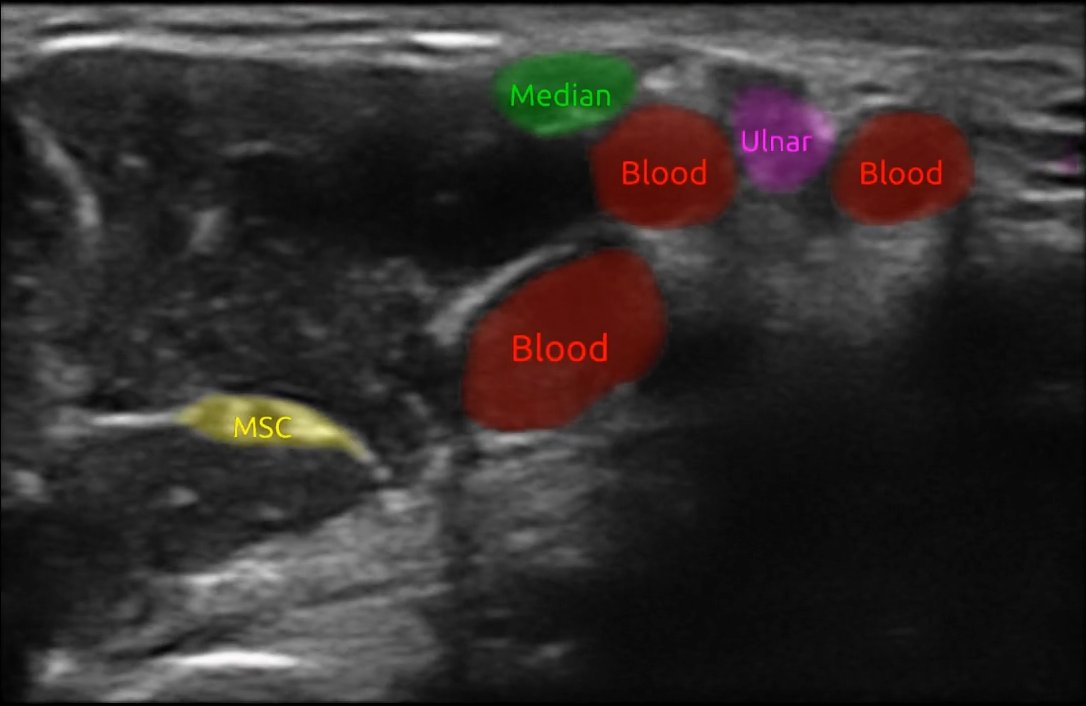

Forskningen vår med bruk av kunstig intelligens på #ultralyd vises idag frem på NRK. #AI #medisin #bildediagnostikk SINTEF Digital St. Olavs hospital nrk.no/trondelag/snar…

Forskningen vår med bruk av kunstig intelligens på #ultralyd vises idag frem på NRK. #AI #medisin #bildediagnostikk <a href="/SINTEFdigital/">SINTEF Digital</a> <a href="/StOlavshospital/">St. Olavs hospital</a>

nrk.no/trondelag/snar…